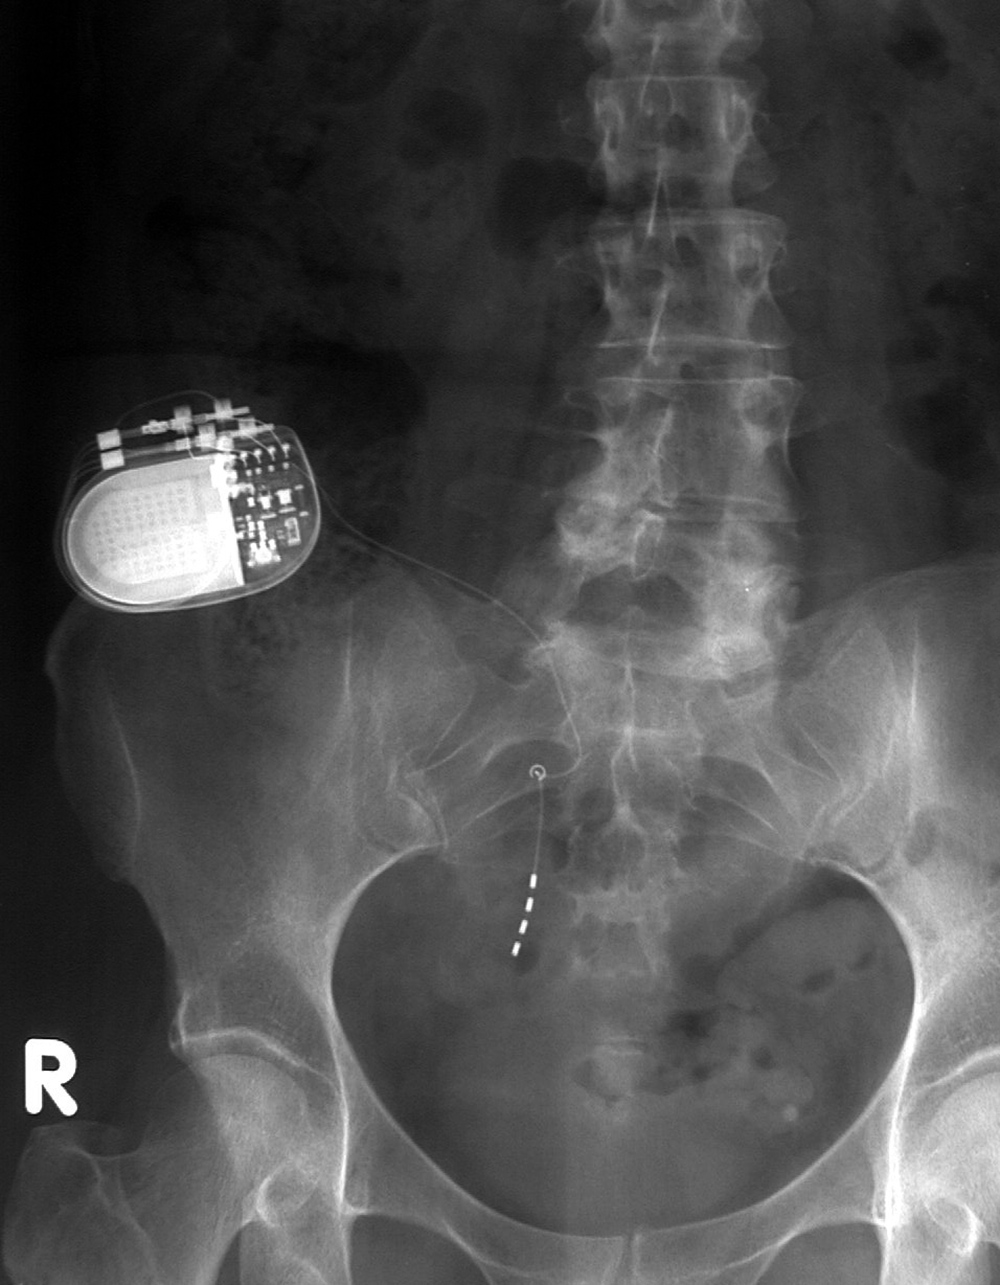

| Lumbar spine pedicle plates and screws and Brantigan disk cage (arrow) |

Brantigan disk cage |

| Note the associated solid posterolateral bony fusion masses |

|

From Hunter, 1994 |